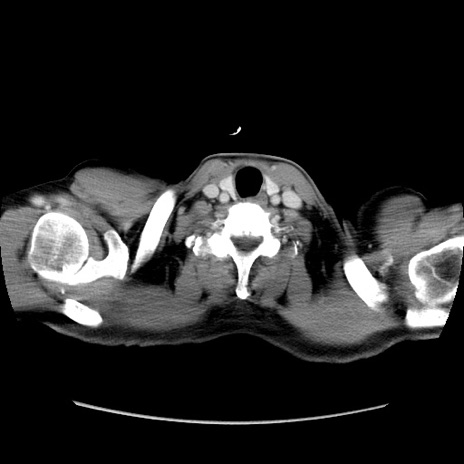

症例34(横断像)

【症例】60歳代 男性

【主訴】右鼠径部膨隆

【現病歴】1年程前より右鼠径部膨隆あり。自己にて還納可能だったため放置していた。3時間前より右鼠径部の脱出を認め、還納困難となり受診。

【既往歴】高血圧

【身体所見】右鼠径部に小児頭大の膨隆あり。弾性硬であり、用手還納は困難。左鼠径部にも膨隆を認める。脱出はなし。